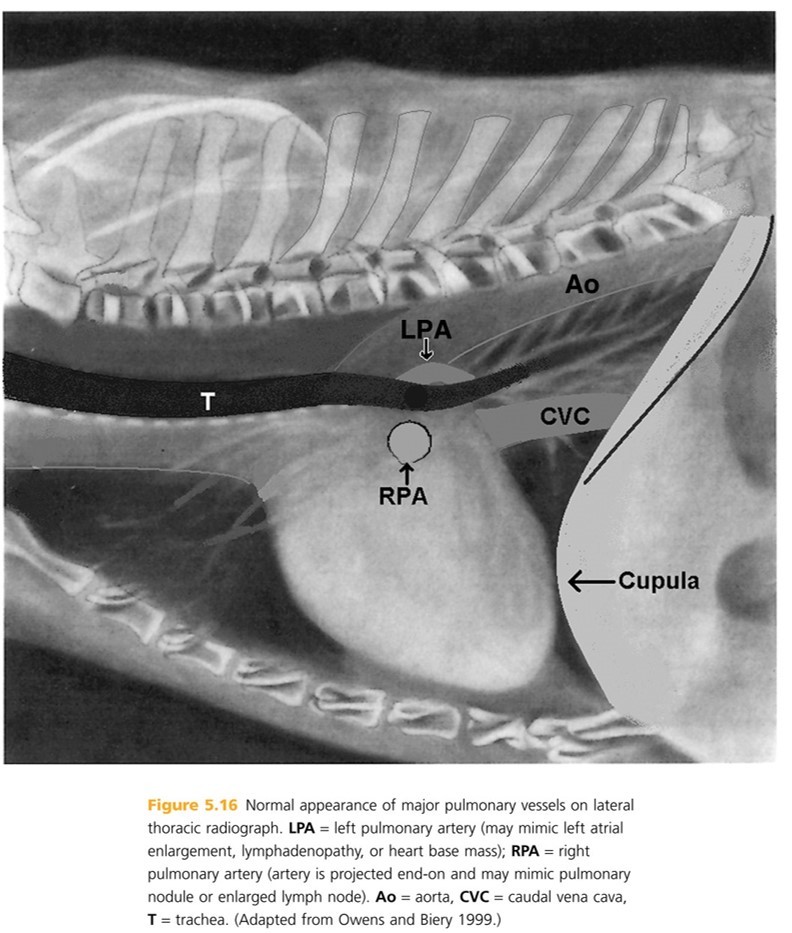

Older cats loose the elasticity of the aortic wall resulting in an altered appearance to cardiovascular structures. The heart moves more ____ to the sternum and the aortic arch b/c more prominent (described as “____” or “_____”) and may be mistaken for a cranial mediastinal or pulmonary mass on (_____ radiographs). On _____ radiographs, the desecending aorta appears more tortuous, wavy , or redundant

parallel

Kinked or knuckled

VD/DV- (B)

lateral - (A) BTW, hypertension can also result in a more tortuous descending aorta

Main pulmonary artery segments (pulmonary trunk) arises near the heart base, ___ of the aorta). Not often identiied on lateral rads (blends with adjacent cardiovascular structures). Right pulmonary artery commonly appears as a rounded soft tissue opacity ____ to the tracheal bifucation.

left

ventral (may mimic lymphadenopathy or pulmonary mass) (RPA)

The left pulmonary artery (LPA) may mimic a left atrial enlargement, lymphadenopathy or heart base mass

The caudal vena cava is the only mediastinal structure located in the _____ hemithorax (one side of thorax). It is visible b/t the right hemidiaphragm and the cardiac silhouette in the _____ _____. Phases of cardiac cycle ( includes the diastole, the systole, and the intervening pause) may affect the size of the vena cava, but it is rarely evident on survey rads.

right

caudal mediastinum

The caudal vena cava is normally less than ____ times the width of the aorta (measured at the same intercostal space). Less than the length of the ____ thoracic vertebra. And, wider at the ____ of inspiration, when the intrathoracic pressue is low. Cranial vena cava is NOT normally seen on survey rads.

1.5

6th

height